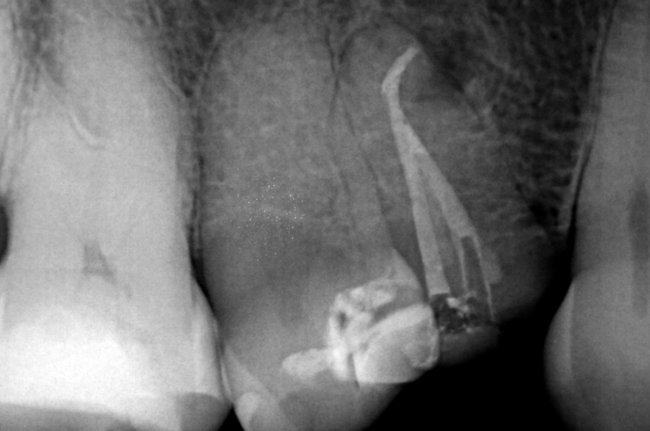

Caso clínico de la Dra. Alessandra Baasch instrumentado con BlueShaper®️+ ApicalShaper®️

Casos ClínicosPor Elena Sanchez10 mayo 2024

La Dra. Alessandra Baasch, especialista en Endodoncia, nos presenta un caso clínico instrumentado con BlueShaper®️+ ApicalShaper®️